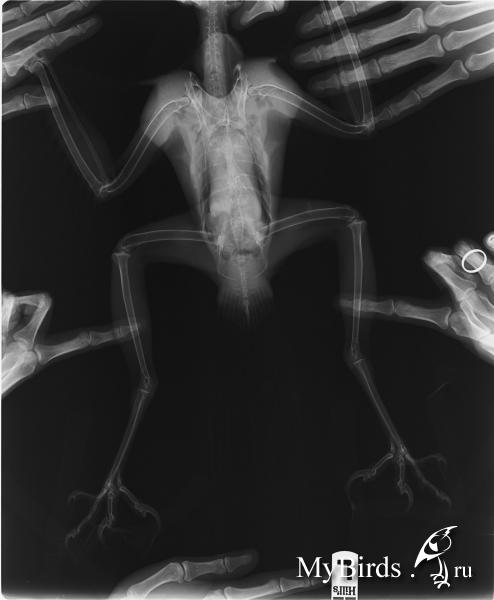

Pticelov Опубликовано 18 февраля, 2013 #100 Опубликовано 18 февраля, 2013 Может быть невнимательно прочитал тему, если так, то прошу прощения.Что у птицы с хвостом? Во время испражнения поднимает? Струя помёта нормальная (0,5 - 1 м)? Если заставить взмахнуть крыльями, хвост раскрывается в веер?У меня был подстреленный тетеревятник, который при падении повредил поясничный отдел (был сильный отёк). Пару недель птица не могла управлять хвостом и одной лапой, испражнялась не по-ястребиному ("под себя").Никого не смущает тёмное пятно а снимке?

Димулька Опубликовано 18 февраля, 2013 Автор #101 Опубликовано 18 февраля, 2013 Струя нормальная. Хвост поднимает, веером и с начала так было. А вот пятнышко и в правду смущает...

Полосатая Опубликовано 18 февраля, 2013 #102 Опубликовано 18 февраля, 2013 Нормальное пятно, как вариант - это лишь небольшое кол-во газов в кишечнике. Вы не на пятно смотрите, а на целостность позвонков - они целые, ровные, позвоночный столб не нарушен.